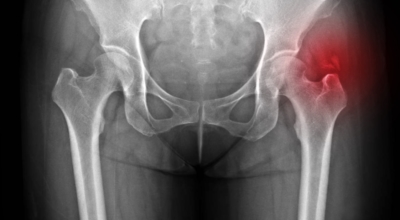

고관절염은 고관절에 나타나는 관절염을 말하며 고관절의 연골이 닳게 되면서 뼈와 뼈가 서로 부딪히며 통증을 일으키게 돼요. 고관절염 초기 증상으로는 사타구니 부위가 불편하게 느껴지며, 무리하면 통증이 발생할 수 있으며, 관절염 증상이 심해지면서 사타구니에서 느끼던 통증이 허벅지와 엉덩이 통증으로 이어지기도 하는데, 고관절염 통증 증상으로 초기에는 허리 통증이 나타나 허리 질환과 혼동하기 쉬우며 각별히 척추질환이 있는 사람은 고관절 통증과 마찬가지로 엉덩이, 다리 통증이 동반되기 때문에 훨씬 헷갈리는 경우가 많습니다.

이 증상은 퇴행성 고관절염에 의해 생기는 현상으로 보통은 중장년층에게 자주 일어나는 질병입니다. 이 질병은 관절과 관절 사이에 존재하는 연골이 닳아 없어지면 관절 내부와 주위에 염증과 통증을 동반합니다. 보통 골반 아래단에 뻐근한 증상을 일으키고 양반다리 자세를 할 때 통증이 심해져요.

더불어 계단을 오를 때 통증이 심해지고 오래 걷는것도 힘들어 져요. 원인은 노화로 인한 연골 마모, 과체중, 고관절 질환을 방치하는 경우 입니다. 치료방법은 적절한 운동과 소염제를 사용하기도 하며 심할경우 수술 치료가 시행 될 수 있어요.

3. 고관절 통증 증상 원인 - 퇴행성 관절염

나이가 들면 예사로 발생되는 질환 중 한 종류입니다. 관절을 지켜주고 있는 연골의 손상이나 퇴행성 변화로 인해 관절을 이루는 뼈와 인대 등에 손상이 생겨 염증과 통증이 나타나는 질환입니다. 고관절 쪽 연골이 닳게 되면서 망가지게 되고 또 쉽게 없어지지 않는 통증에 시달릴 수 있답니다.